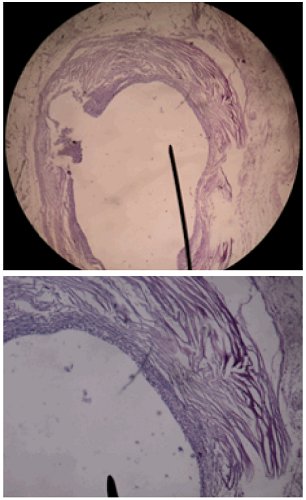

La Figura 5 corresponde a una paniculitis mixta sin vasculitis con reacción granulomatosa focal y fibrosis reactiva circundante; formaciones quísticas en tejido celular subcutáneo de paredes fibrosas, recubiertas en su cara interna por macrófagos y células epitelioides a cuerpo extraño. Estos hallazgos son compatible con cisticercosis subcutánea.